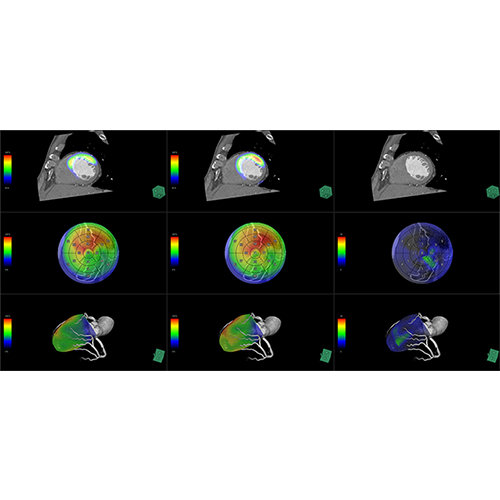

ANYTHINK 经导管主动脉瓣膜置换术分析系统